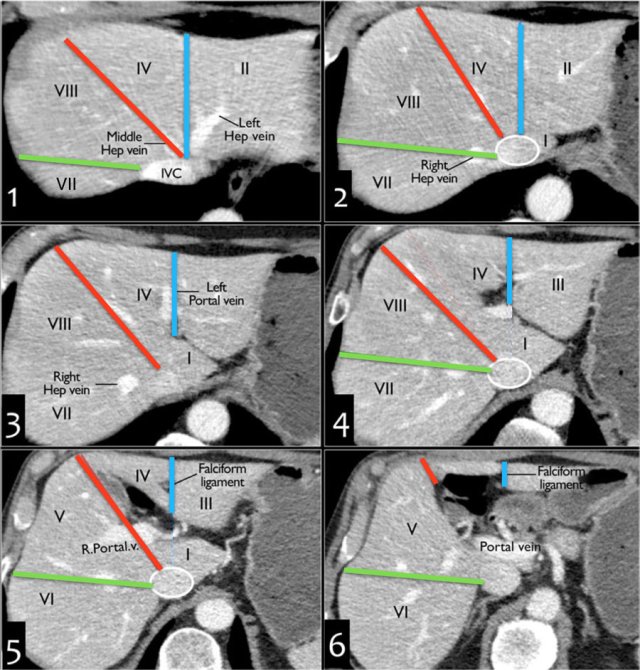

Transverse anatomy

This figure is a transverse image through the superior liver segments, that are divided by the right and middle hepatic veins and the falciform ligament.

This is a transverse image at the level of the left portal vein.

At this level the left portal vein divides the left lobe into the superior segments (II and IVa) and the inferior segments (III and IVb).

The left portal vein is at a higher level than the right portal vein.

This image is at the level of the right portal vein.

At this level the right portal vein divides the right lobe of the liver into superior segments (VII and VIII) and the inferior segments (V and VI).

The level of the right portal vein is inferior to the level of the left portal vein.

At the level of the splenic vein, which is below the level of the right portal vein, only the inferior segments are visible.

How to separate liver segments on cross sectional imaging

Left liver: lateral(II/III) vs medial segment (IVA/B)

Extrapolate a line along the falciform ligament superiorly to the confluence of the left and middle hepatic veins at the IVC (blue line).

Left vs Right liver: IVA/B vs V/VIII

Extrapolate a line from the gallbladder fossa superiorly along the middle hepatic vein to the IVC (red line).

Right liver: anterior (V/VIII) vs posterior segment (VI/VII)

Extrapolate a line along the right hepatic vein from the IVC inferiorly to the lateral liver margin (green line).